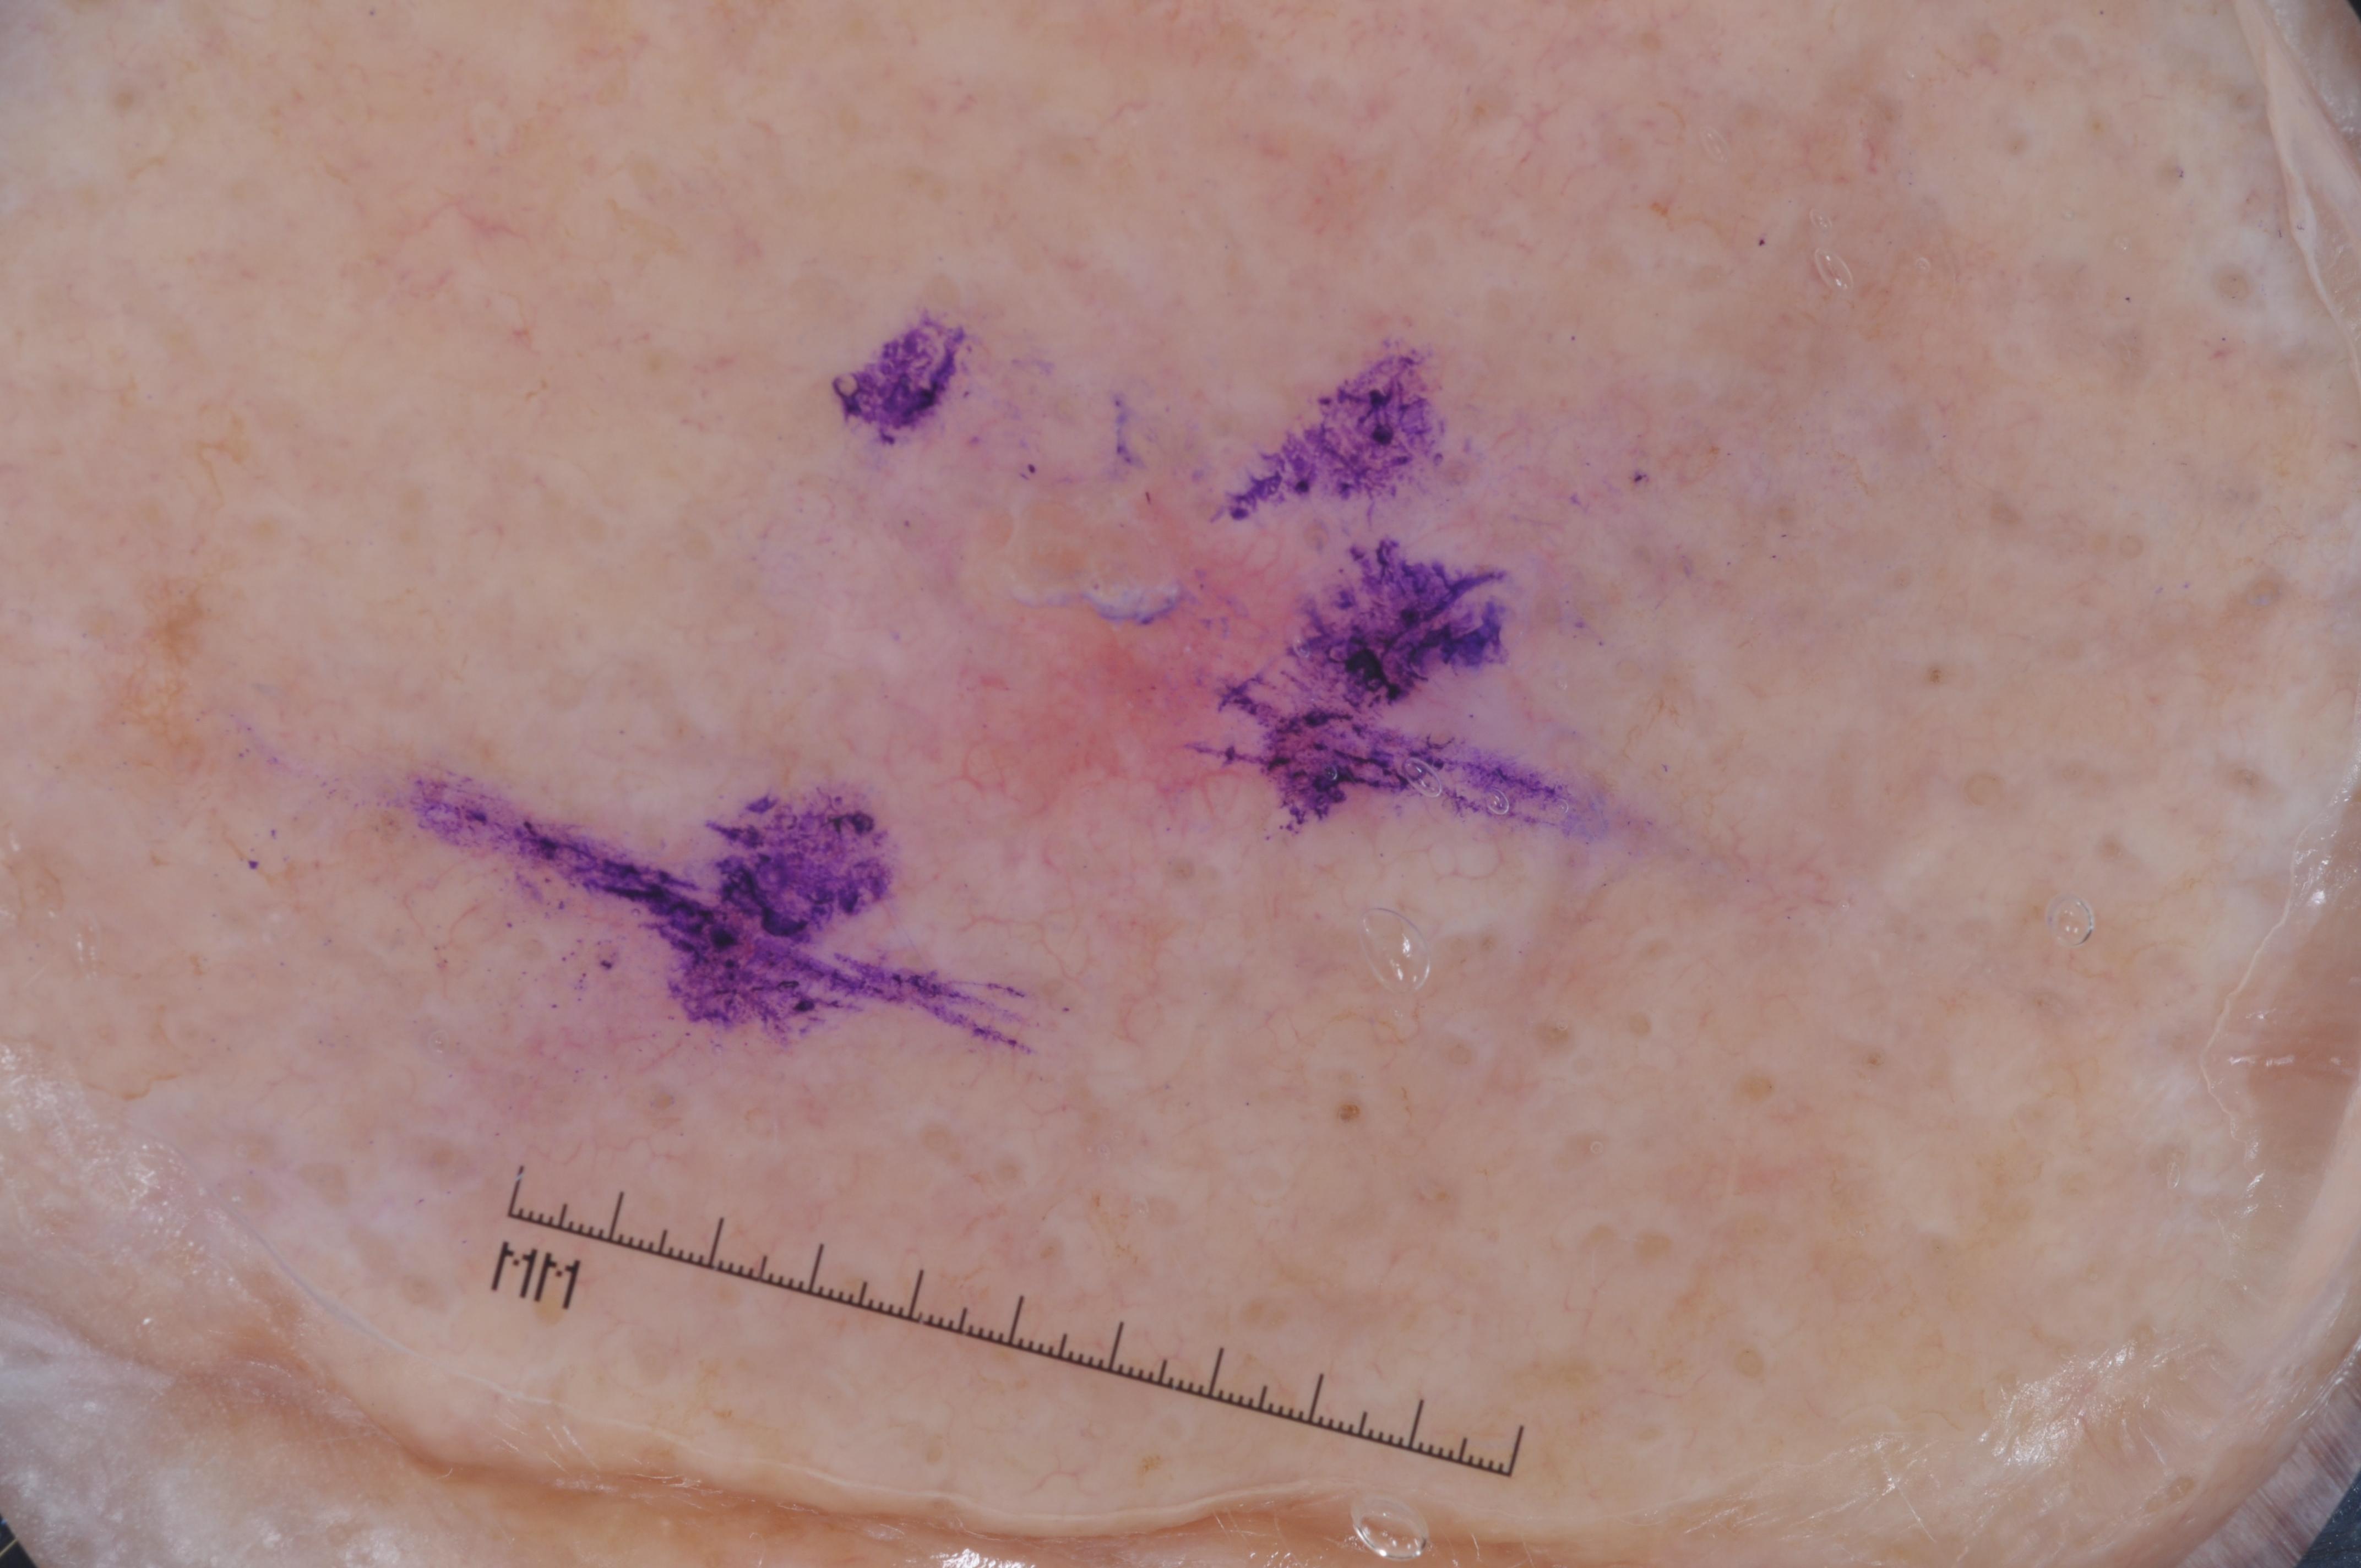

ISIC-DICM-17K (ISIC Dermoscopic Images and Clinical Metadata 17K) is a curated and balanced dataset derived from the International Skin Imaging Collaboration (ISIC) Archive Gallery. It comprises 17,060 dermoscopic images and clinical metadata (8,530 melanoma and 8,530 non-melanoma classes).

For more details, please follow the project’s GitHub repository: https://github.com/mmu-dermatology-research/isic-dicm-17k

This dataset was used in this study and benchmark to explore the effectiveness of multimodal learning for skin lesion classification:

S. Ahammed, X. Cui, W. Lu and M. H. Yap, "Skin Lesion Classification using Dermoscopic Images and Clinical Metadata: Insights from Multimodal Models," 2025 IEEE/CVF Conference on Computer Vision and Pattern Recognition Workshops (CVPRW), Nashville, TN, USA, 2025, pp. 222-230, DOI: 10.1109/CVPRW67362.2025.00027